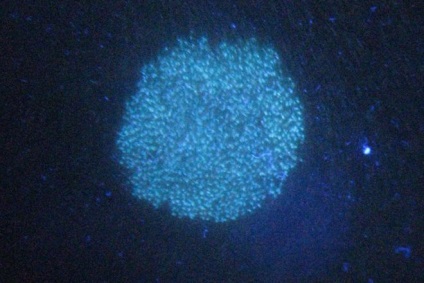

A diagnózis és a kezelés ótvar van a hatáskörébe bőrgyógyászok és trichologists. Először is, a szakértő értékeli a megjelenése tüzet. Ha a beteg még kopaszság az egész fej bőrt, felveti a mikroszkópia és egyenetlen ritkuló haj és a jelenléte fekete foltok között jelzi trihofitii. Ahhoz, hogy vizsgáljuk meg a fejbőr egy speciális lámpa Wood. Ennek fényében a gombás sejtek érzékenyek a fényre. Mikroszkóp van egy fényes zöld színű, és trihofitia - kék és fehér.